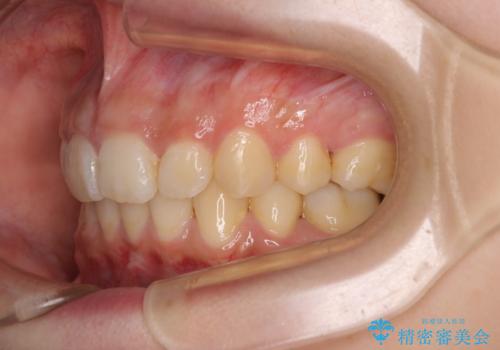

下顎前歯が隠れて突出した口元 ワイヤー装置での抜歯矯正

- 前歯のデコボコと口元の突出感を気にして来院された患者様です。

下顎骨の左右差や、上顎骨の前方位などが認められたため、上下左右の第1小臼歯4本を抜歯し、ワイヤー装置にて矯正治療を行うこととしました。

骨格的な左右差がありましたが、何とか当初予定していた期間で、左右対称の咬み合わせに仕上げることができました。